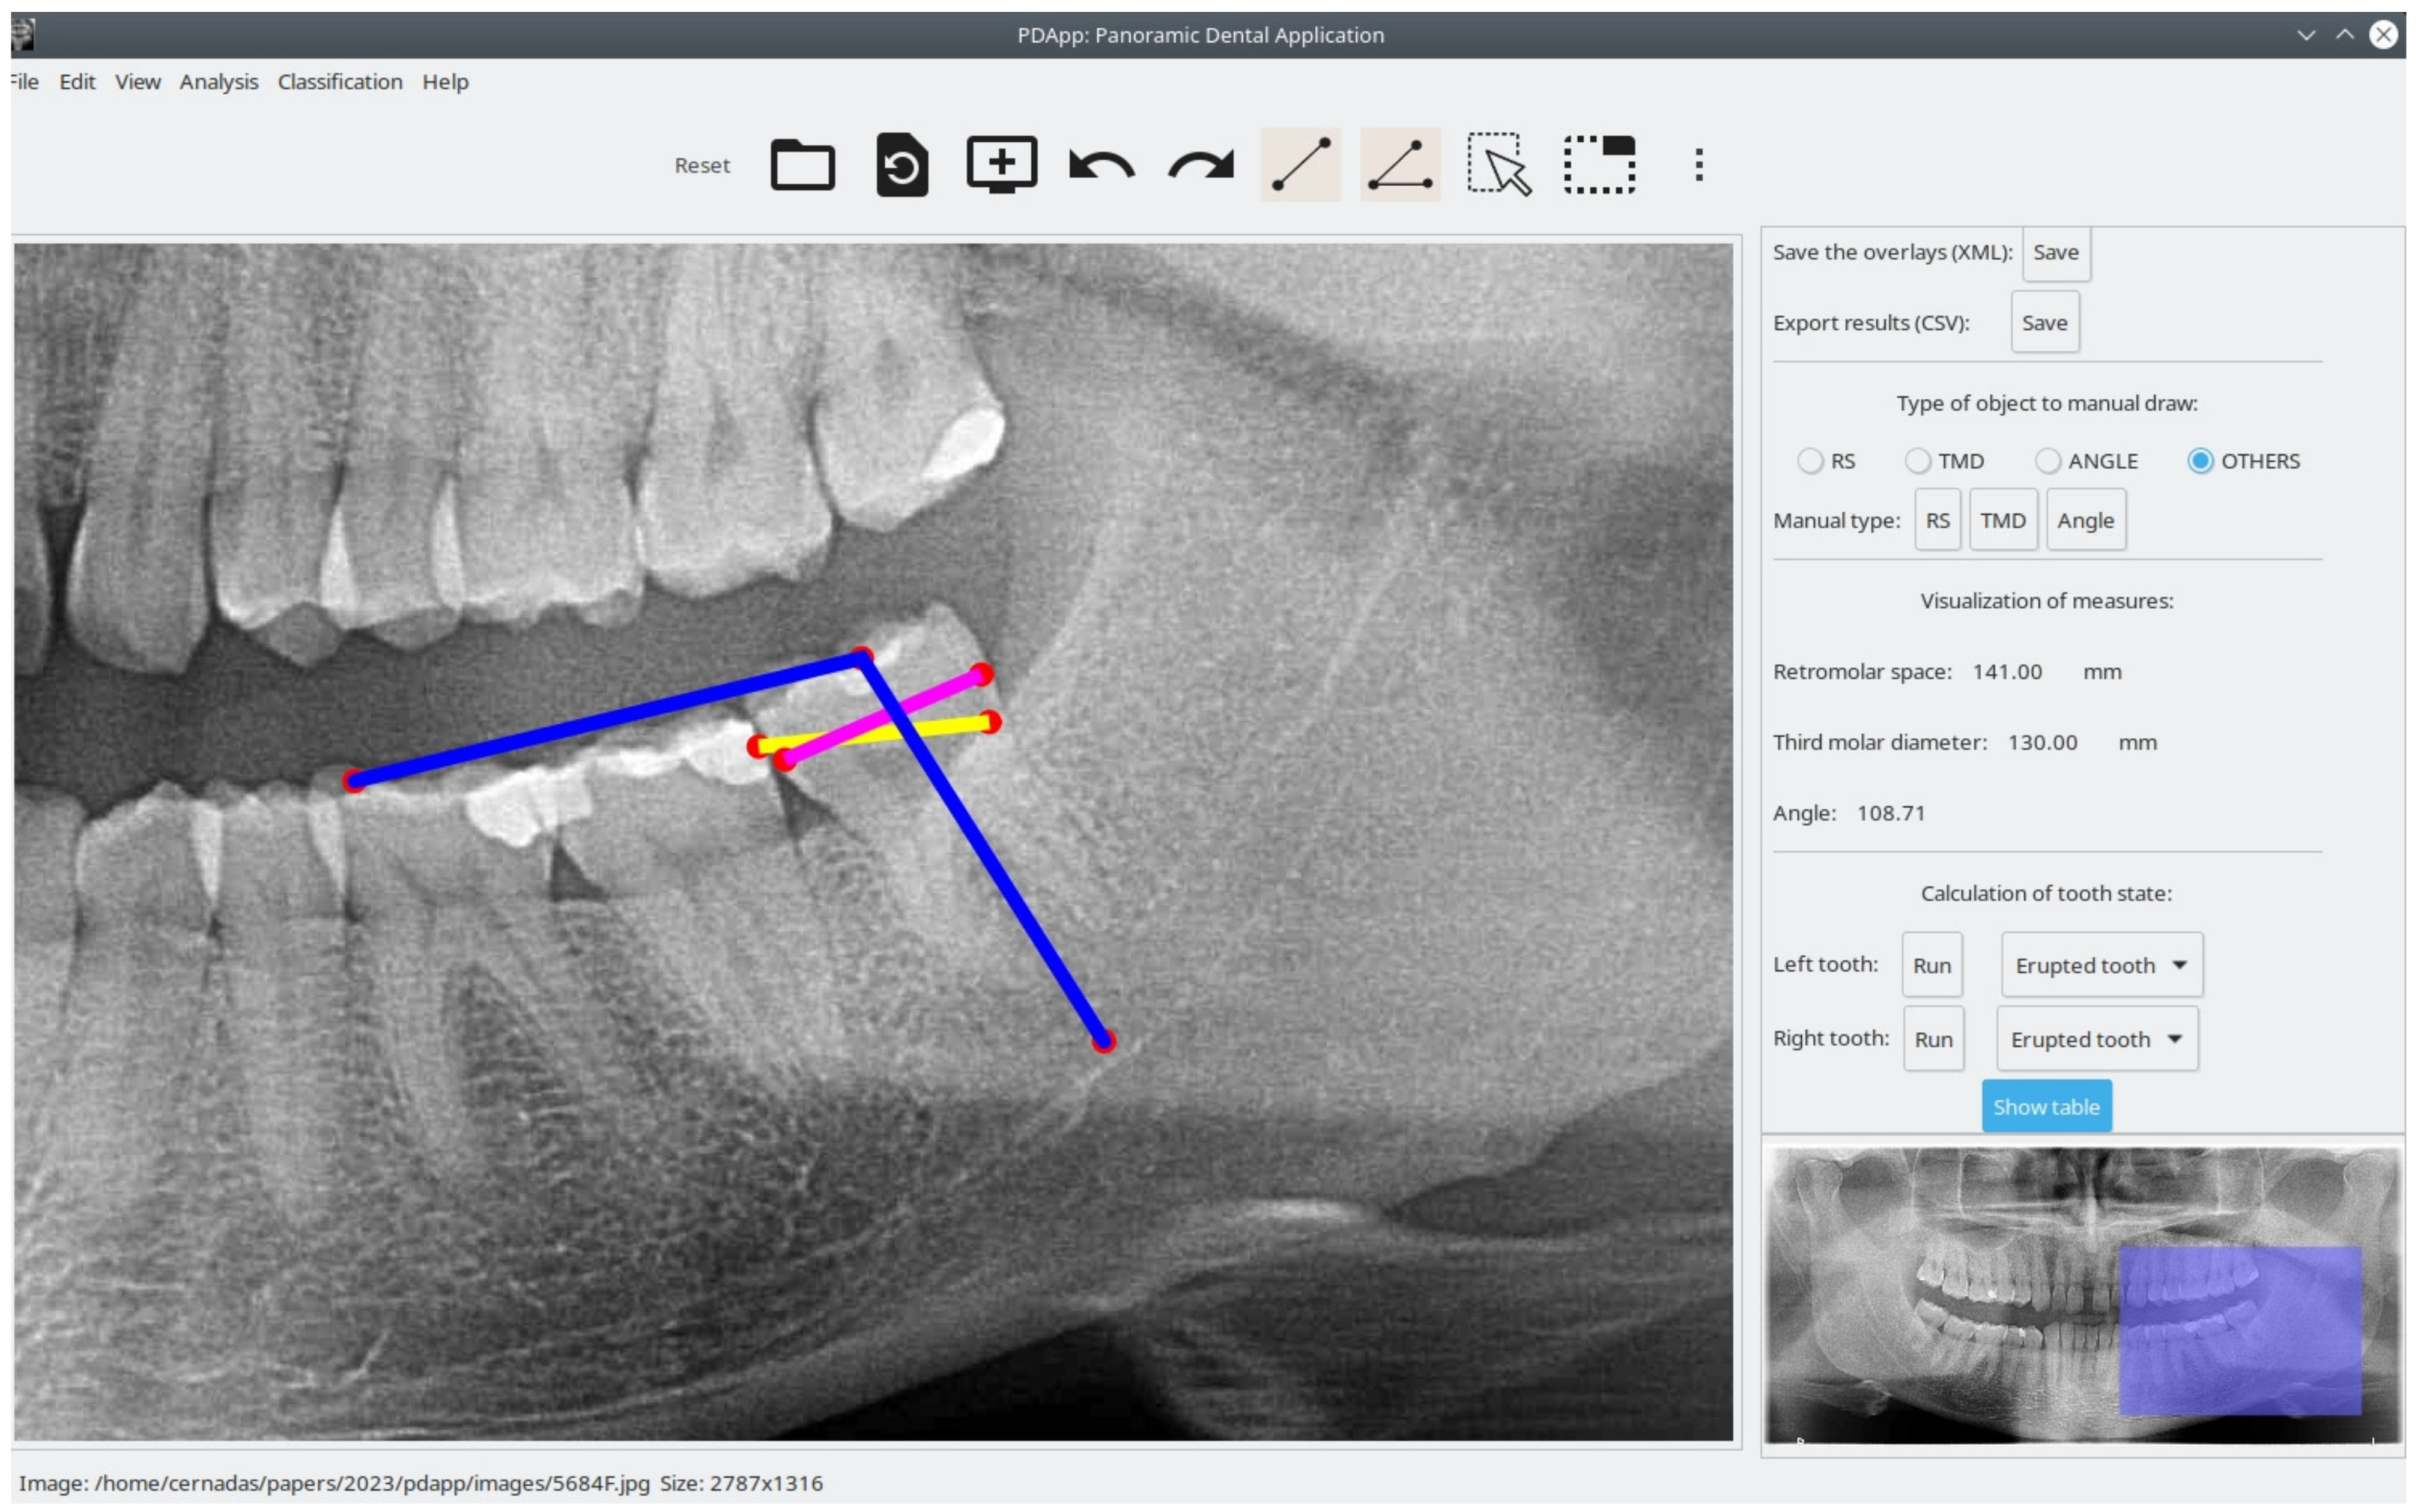

Panoramic Dental Application (PDApp) is a desktop tool that runs on a general-purpose computer under the Linux and Windows operating systems. It was written in the C++ programming language using the GIMP Tool Kit (GTK+) library (https://www.gtk.org/ (accessed on 16 February 2023)) to develop the GUI. Figure 1 shows the GUI of PDApp with a typical radiological image loaded, processed, and reviewed by a dental expert and with the lateral panel displayed.

Figure 1. Screenshot of PDApp v.1 software with analysis of typical panoramic radiograph and lateral panel open. In the right molar, the pink line represents third molar diameter, the yellow line represents retromolar space, and blue lines represent the angle. Measurement of the left molar (violet objects) are shown in the lateral panel.